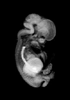

Carnegie Stage 22 (54 post-ovulatory days)

Most embryos at stage 22 are approximately 54 postovulatory days old and measure 25-27 mm in length. Distinguishing criteria for this stage include clear formation of the external ear, the hands begin to extend ventrally beyond the body wall, the fingers of one hand may overlap the fingers of the opposite hand, thickened eyelids just begin to cover the outer margins of the eye, and the superficial vascular plexus of the head now extends about three-quarters of the way above the eye-ear level.

Animations